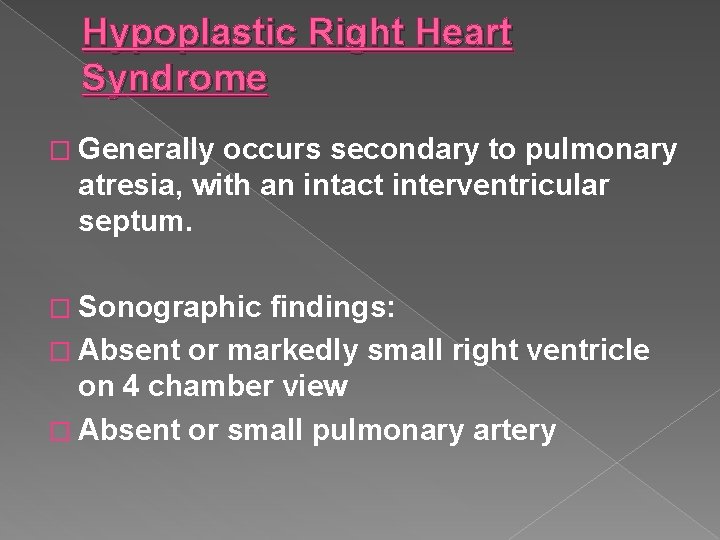

Hypoplastic Right Heart Syndrome � Generally occurs secondary to pulmonary atresia, with an intact interventricular septum. � Sonographic findings: � Absent or markedly small right ventricle on 4 chamber view � Absent or small pulmonary artery

Hypoplastic right heart syndrome › Absent or markedly small right ventricle on 4 chamber view › Absent or small pulmonary trunk